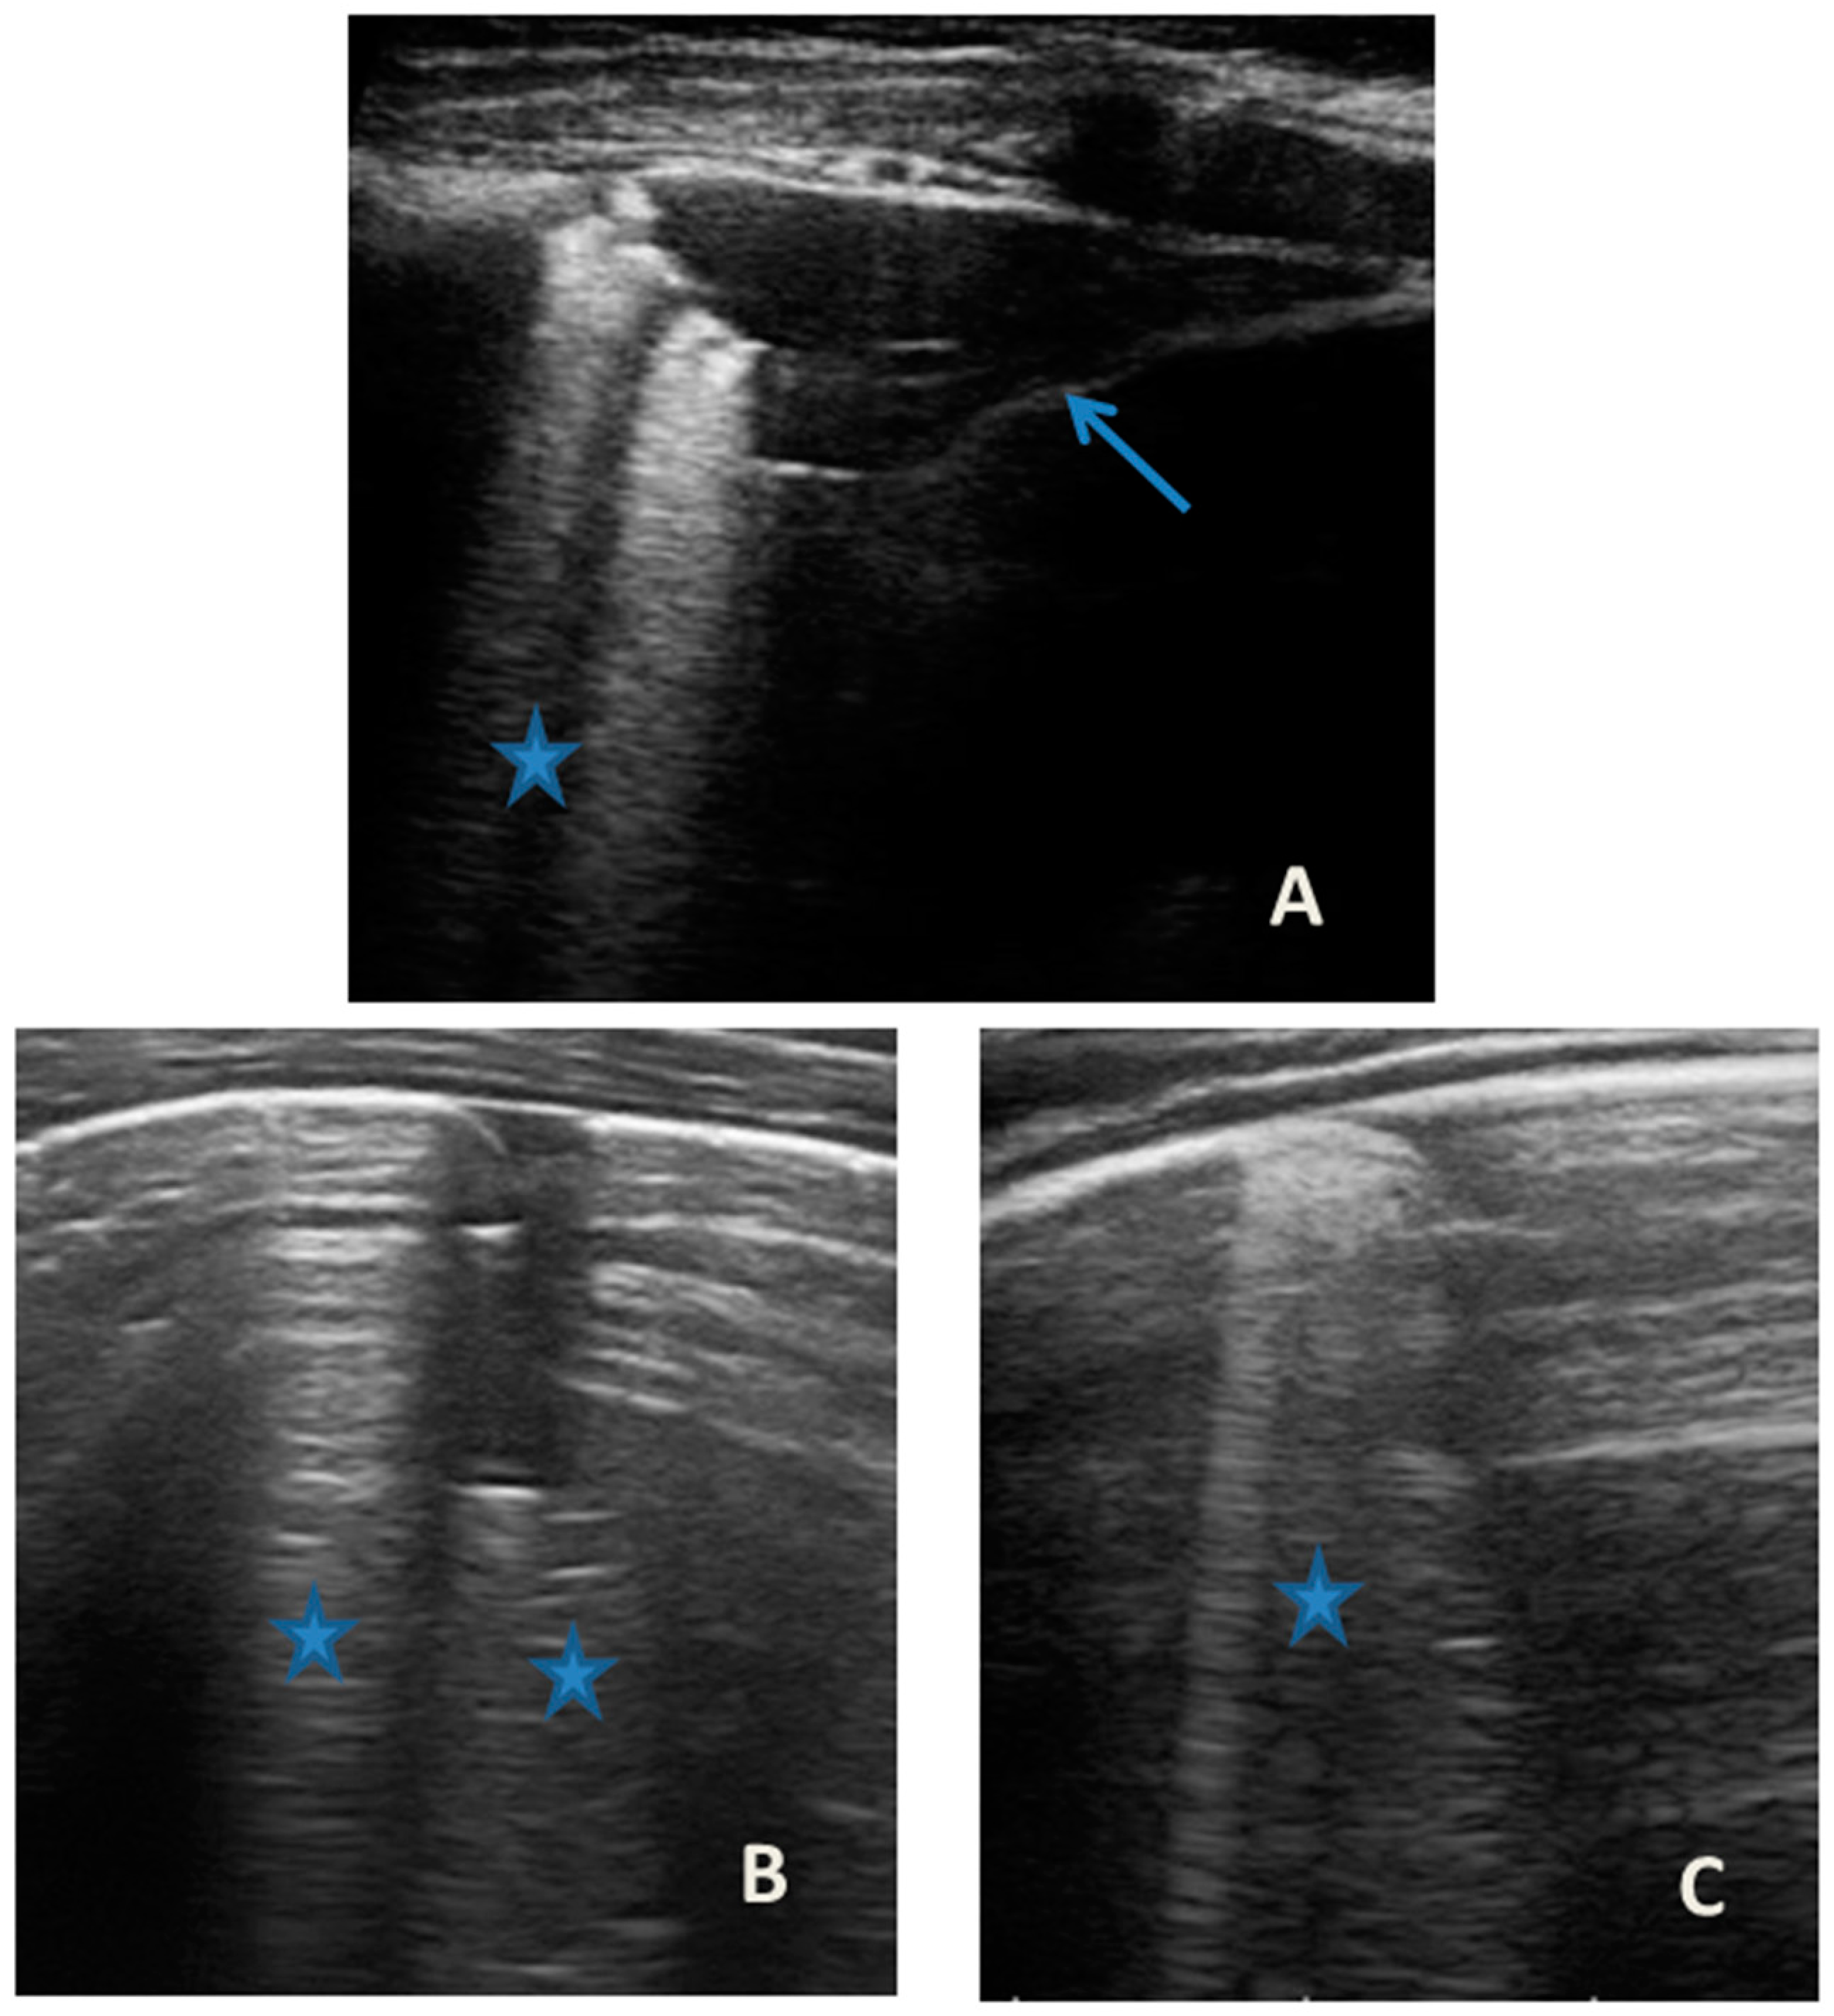

She came to our attention at the PED for acute onset of asthmatic bronchitis, with mild respiratory distress, fever, and rhinitis present for three days. She was mildly dyspneic, in good general condition, and with stable vital signs. She did not need oxygen. Upon examination of the chest, she presented with diffuse bronchospasm, associated with rales spread throughout the lung area. She had a moderate rise in the inflammation indices. At the same time as the first clinical evaluation, we performed LUS, which showed a picture compatible with acute inflammation of the small airways (Figure 7). This picture was also confirmed by the microbiological data of positivity of the nasopharyngeal swab for RSV. Respiratory symptoms resolved after 72 acute phase therapy. The patient was discharged with the preventive therapy already in progress. LUS follow-up showed the complete resolution of the ultrasound picture after a total of 5 days.

Figure 7.

Grayscale lung ultrasound examination shows: (A): sub-centimeter consolidations less than 0.5 cm in size (arrows), associated with confluent artifacts (asterisks) in the left lateral mid-apical area; (B): a small consolidation of 0.5–1 cm (arrows), with elements of dynamic air bronchogram (arrowhead) (as per suspected inflammation) [10,14,15], associated with a circumscribed area of “white lung” (asterisks) in the right middle apical area; (A,B): irregularity of the pleural line. Picture compatible with acute inflammation of the small airways of viral origin [14,15].

In our cases (Table 1), particularly in the first three cases—children with asthma not controlled due to an inadequate preventive therapy for age, phenotype, and severity of the clinical picture [1,2]—LUS was highly positive (Figure 1, Figure 3 and Figure 5). It showed the presence of lung atelectasis, which resolved slowly after weeks of therapy of the acute attack and the beginning of adequate preventive therapy. On the contrary, in case 4 and 5—children with asthma well controlled by adequate preventive therapy—LUS was not highly positive (Figure 6 and Figure 7). In fact, it did not show large atelectasis, but a slight SIS in case 4, and a SIS suggestive of viral infection of the small airways in case 5 [14,15].